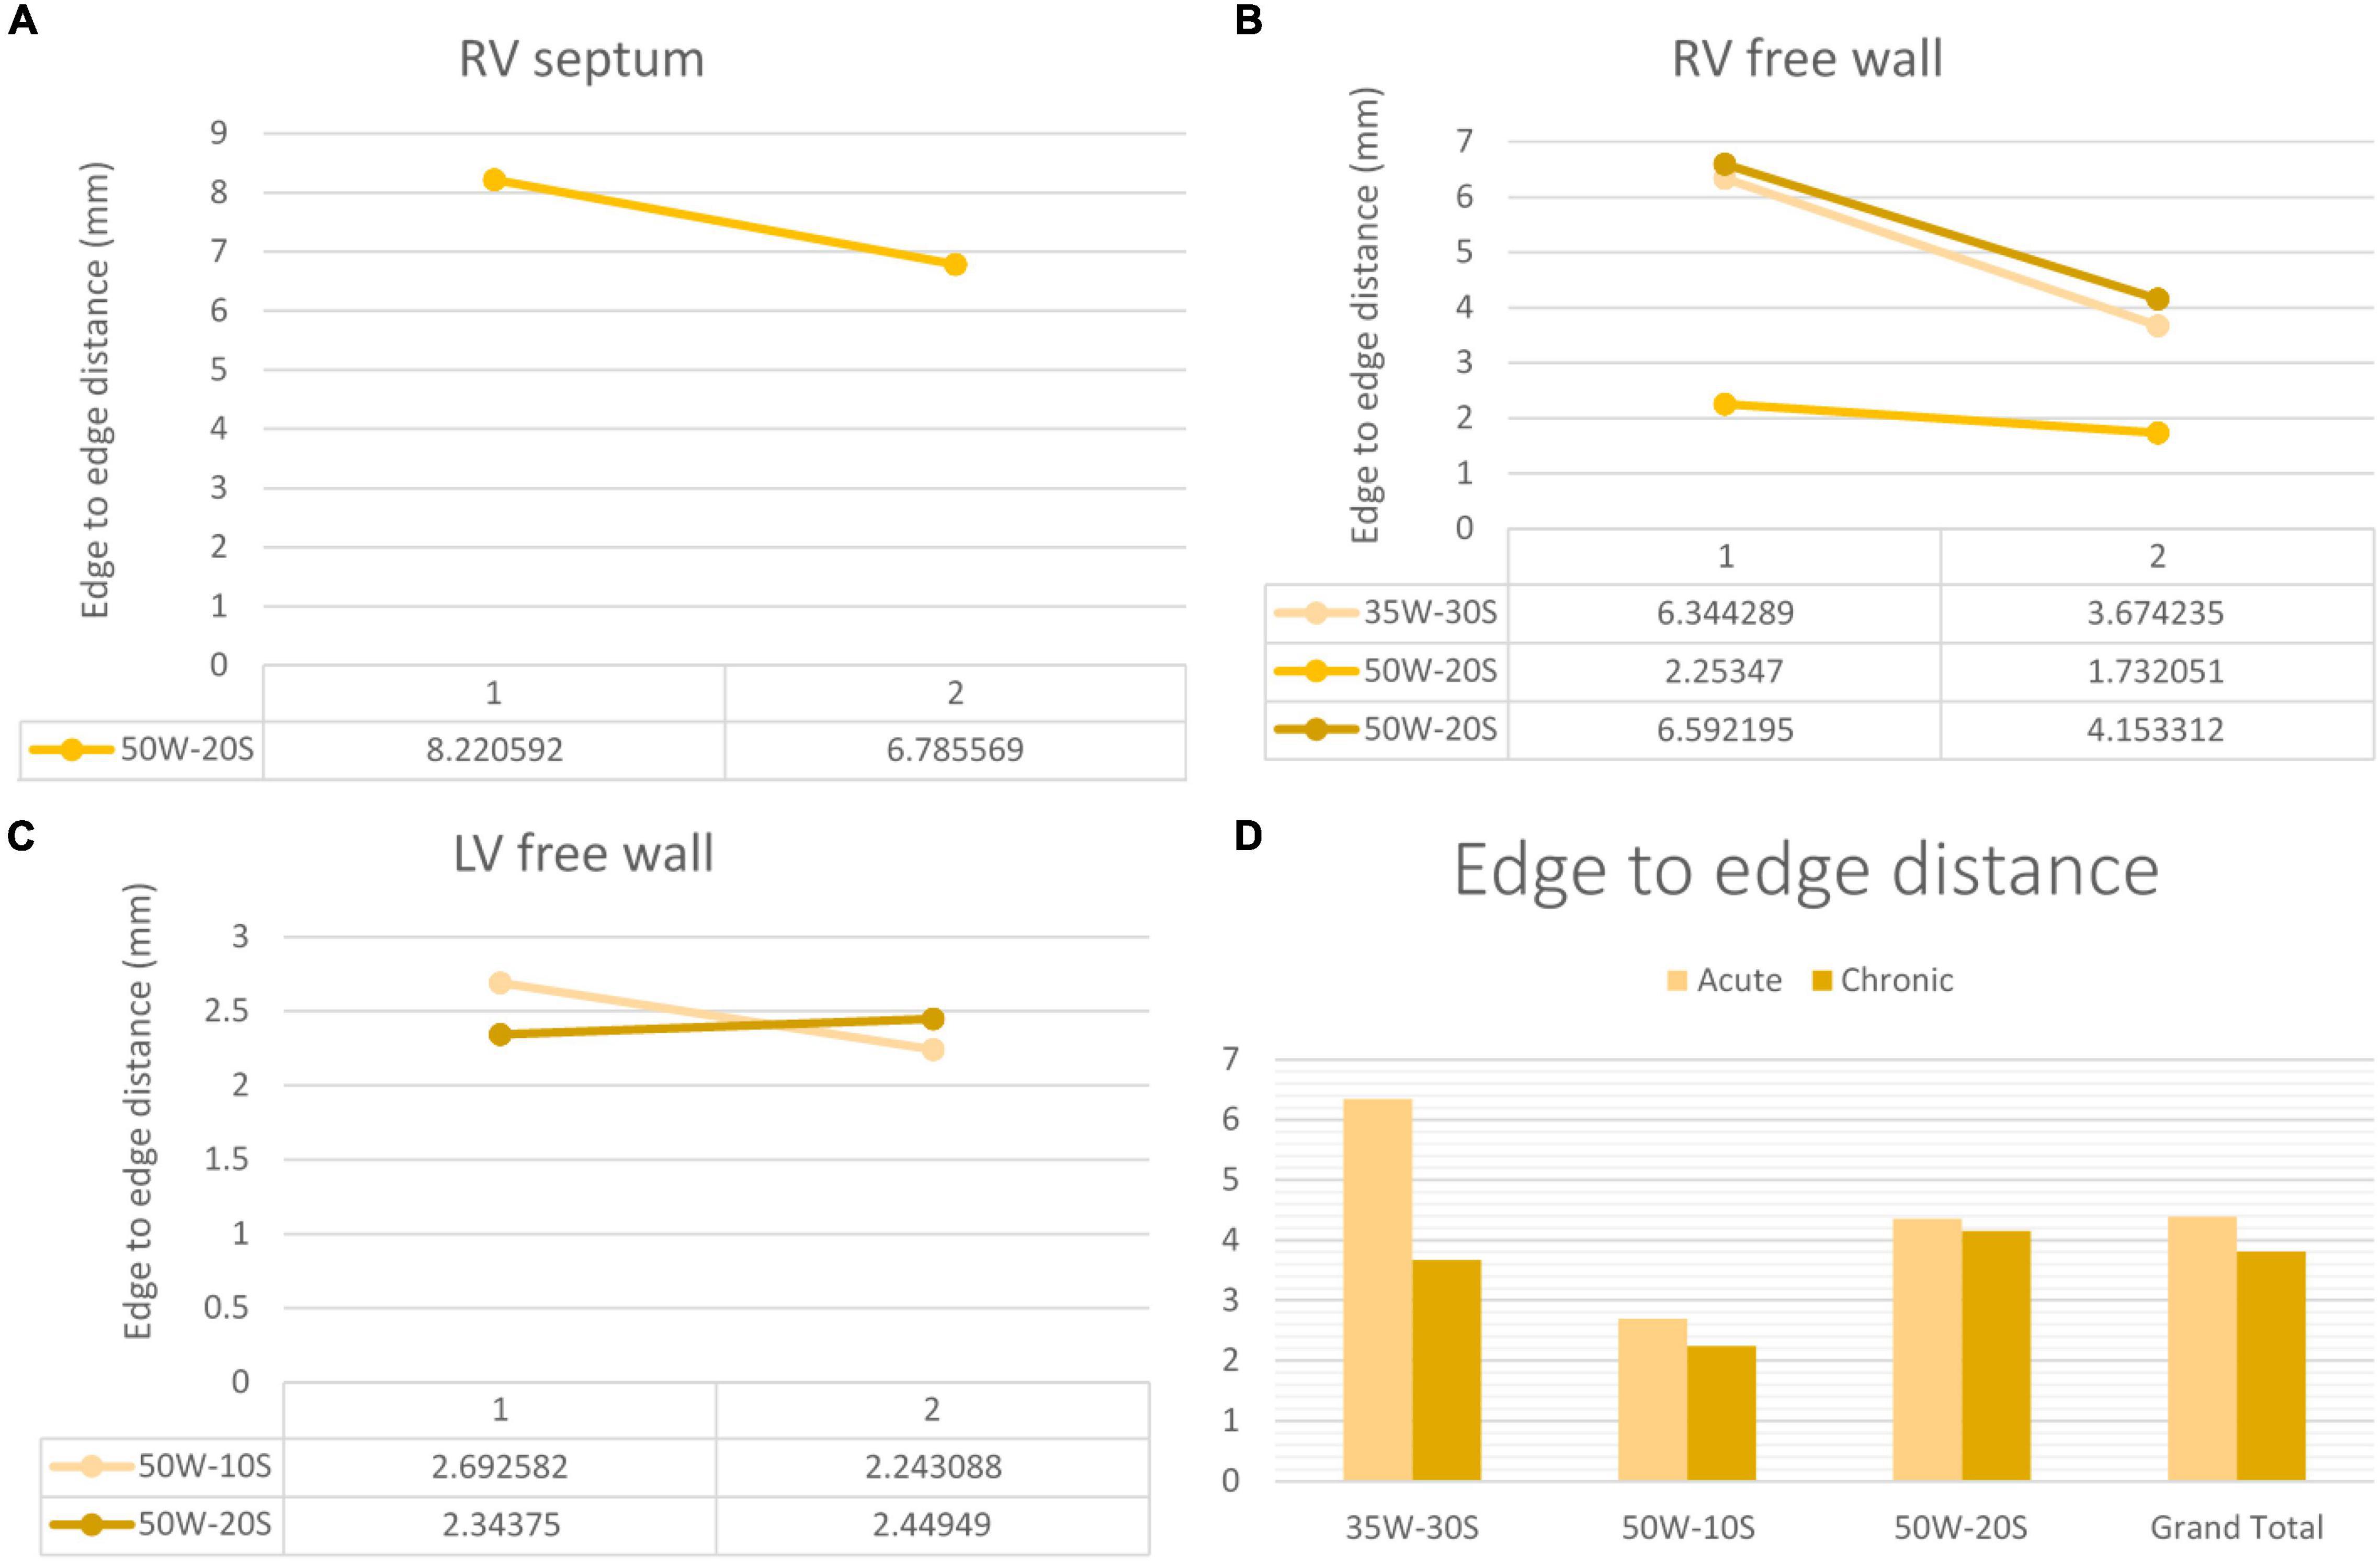

d- Distances Measured on LGE-MRI in Unconnected Lesions:

The average center-to-center distance between unconnected lesions as quantified by LGE-MRI was 24.27 ± 1.60 mm and 23.15 ± 2.91 mm at the acute and chronic stages, respectively. In addition, the edge-to-edge distance between these paired lesions as quantified by LGE-MRI at the acute and chronic stages were 4.35 ± 1.27 mm and 4.15 ± 0.95 mm, respectively. Center-to-center and edge-to-edge distances were reported on a limited number of paired lesions where clear lesion contours allowed calculation of such distances: Therefore, performing statistical analyses on these corresponding pairs was not possible due to the very limited number of pairs. No p-values were calculated.

Edge to edge distance and center-to-center distances are shown in Figures 6, 7, respectively. According to our findings, lesions created in RV free wall and septum have little to no reduction in center-to-center distance. Instead, they demonstrate a small decrease in their edge-to-edge distance. However, lesions created in the LV tended to have a larger reduction in center-to-center distance with no change in their edge-to edge-distance.

Figure 6. Center-to-center distance progression at varying doses and regions within the heart determined by MRI. The variation in center-to-center distance between the acute and chronic settings is shown in the RV septum (A), RV free wall (B) and LV free wall (C). Overall average of acute and chronic center-to-center distance between lesions created at varying ablation parameters (D). Every line in each graph represents the variation of center-to-center distance between one pair of ablation points (50W-20S are shown twice as two pairs were created using this parameter). For instance, in the LV free wall, the center-to-center distance reduced from 21 to 9.3 mm from the acute to chronic settings in a pair of lesions. Another pair reduced from 24.9 to 17 mm.

Figure 7. Edge-to-edge distance progression at varying doses and regions within the heart determined by MRI. The variation in edge-to-edge distance between the acute and chronic settings is shown in the RV septum (A), RV free wall (B) and LV free wall (C). Overall average of acute and chronic edge-to-edge distance between lesions created at varying ablation parameters (D). Every line in each graph represents the variation of edge-to-edge distance between one pair of ablation points (50W-20S are shown twice as two pairs were created using this parameter) For instance, in the RV septum in panel (A), the edge-to-edge distance reduced from 8.2 to 6.8 mm from the acute to chronic settings in a pair of lesions.

Lesion Size Regression

Our investigation is the first to study lesion evolution by looking at center-to-center and edge-to-edge distances. In the septum and RV free wall, edge-to-edge distances became smaller with time, but center-to-center distances stayed relatively constant. This can be explained by the time dependent resolution of edema and shrinkage of the lesion. However, in the LV free wall, even center-to-center distance became smaller. This suggests a greater degree of edema in the LV free wall compared to other locations. A possible explanation to this finding is that higher strain and contractile forces in the LV could lead to higher degrees of edema (14).